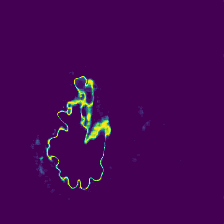

Diffusion models have shown impressive performance for generative modelling of images. In this paper, we present a novel semantic segmentation method based on diffusion models. By modifying the training and sampling scheme, we show that diffusion models can perform lesion segmentation of medical images. To generate an image specific segmentation, we train the model on the ground truth segmentation, and use the image as a prior during training and in every step during the sampling process. With the given stochastic sampling process, we can generate a distribution of segmentation masks. This property allows us to compute pixel-wise uncertainty maps of the segmentation, and allows an implicit ensemble of segmentations that increases the segmentation performance. We evaluate our method on the BRATS2020 dataset for brain tumor segmentation. Compared to state-of-the-art segmentation models, our approach yields good segmentation results and, additionally, detailed uncertainty maps.